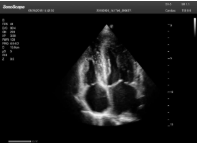

2相控陣探頭

探頭面是平面,接觸面小,近場視野最小,遠場視野大,成像視野呈扇形,適用于心臟。

心臟探頭通常按應用人群劃分為成人、兒童、新生兒三類:(1)成人心臟位置最深、搏動速度慢;(2)新生兒心臟位置較淺、搏動速度最快;(3)兒童心臟的情況介于新生兒與成人之間。

肥厚性心肌病-心尖四腔